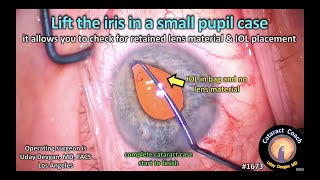

Iris hooks for small pupil - Stop and chop phaco with IOL. Abdo Karim Tourkmani, FEBOphth CataractCoach™ 1673: lift the iris in a small pupil case

CataractCoach™ 1673: lift the iris in a small pupil case Small-pupil-Phaco using IRIS HOOKS : Pradip Mohanta, India, 12th Feb, 2021

Iris hooks for small pupil - Stop and chop phaco with IOL. Abdo Karim Tourkmani, FEBOphth CataractCoach™ 1673: lift the iris in a small pupil case

CataractCoach™ 1673: lift the iris in a small pupil case Small-pupil-Phaco using IRIS HOOKS : Pradip Mohanta, India, 12th Feb, 2021